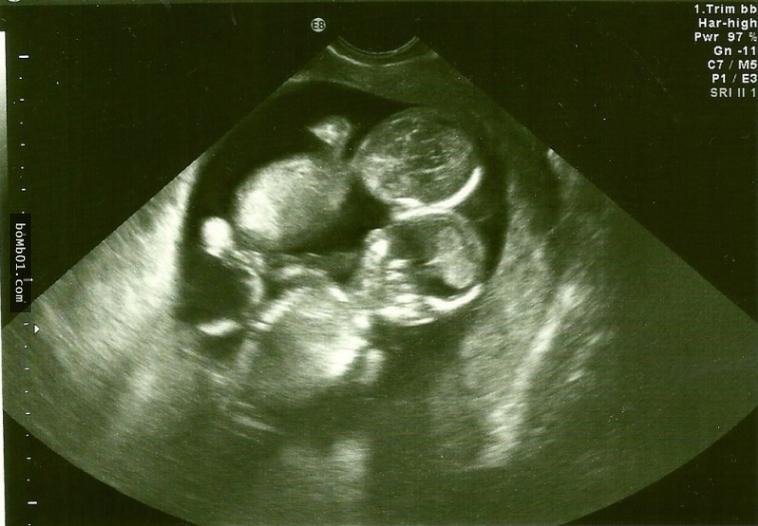

Nhưng chưa vui mừng được bao lâu, Kate đã nhận được thông báo từ bác sĩ, thai nhi bị mắc hội chứng Monoamniotic. Đây là hội chứng xảy ra khi hai bào thai chia sẻ chung một túi ối không màng ngăn khiến dây rốn quấn quanh thai nhi trong quá trình phát triển. Điều này sẽ dẫn đến tình trạng thai thiếu oxy và chết lưu trong bụng mẹ. Xác xuất xảy ra hội chứng Monoamniotic này là 1% và tỷ lệ sống sót chỉ đạt 50%.

Bác sĩ đề nghị Kate không nên công khai tin cô có thai vì tình trạng thai nhi phát triển không tốt lắm. Nghe xong, Kate đã rất bàng hoàng, tuy nhiên cô vẫn ôm một tia hy vọng rằng hai bé sẽ bình an vô sự. Sau khi thai nhi được 28 tuần, cô bắt đầu nằm viện và lên kế hoạch mổ đẻ ở tuần 32.

Đến ngày sinh, Kate và gia đình vô cùng lo lắng. Nhưng khi tiến hành mổ đẻ, bác sĩ không khỏi kinh ngạc trước cảnh tượng: Dây rốn của cặp song sinh bị quấn vào nhau giống như tết tóc. Nhưng nó cũng không gây cản trở em bé hấp thu chất dinh dưỡng, hai bé gái đều ra đời thuận lợi.